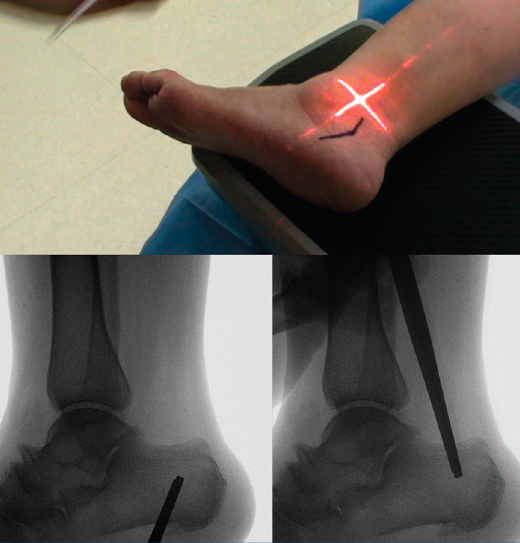

Se marca sobre la piel la osteotomía propuesta utilizando el fluoroscopio; para ello, es necesaria una imagen lateral del tobillo (se debe visualizar completamente superpuesto el lado medial y lateral de la cúpula astragalina). Para evitar lesiones vasculonerviosas, se ha descrito una zona segura que comprende desde la línea que une la inserción de la fascia plantar con la zona posterosuperior de la tuberosidad del calcáneo y una línea paralela situada 11 mm anterior a la primera(12) (véanse las consideraciones de las complicaciones más adelante).

Figura 3. Se realiza bajo fluoroscopia el diseño de la osteotomía y se marca sobre la piel.

Marcamos el vértice de la V en la piel dentro de la zona de seguridad, desde donde marcamos una línea plantar paralela al borde posteroinferior de la tuberosidad y una linea dorsal paralela al borde posterosuperior de la tuberosidad (Figura 3).